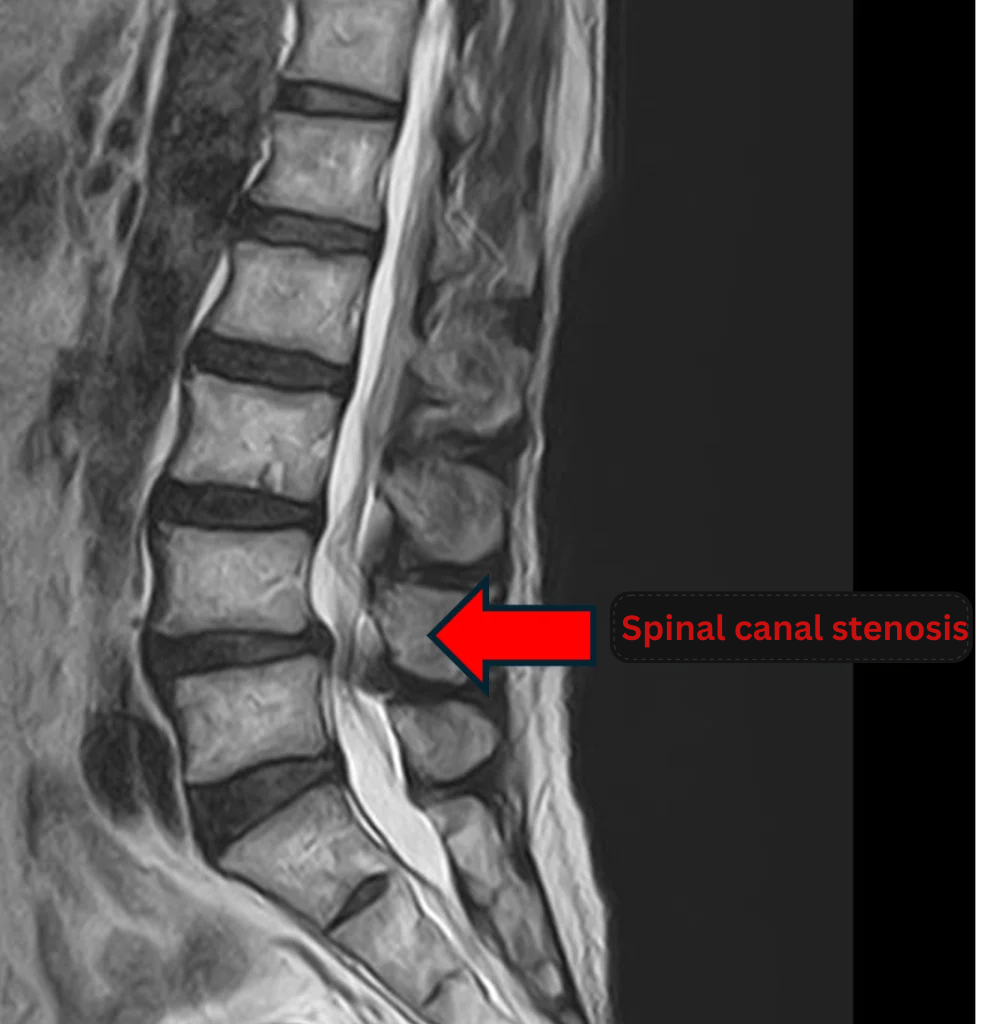

Imaging and findings

- L3/4, L5/S: Disc Degeneration, Bulging.

- L4/5: Disc Degeneration, Bulging, Foraminal Stenosis, Spinal Canal Stenosis, Degenerative Spondylolisthesis.

The above findings were also observed on the imaging.

Compression of the spinal canal caused by disc pathology at L3/4, L4/5, and L5/S was considered the most likely cause of the patient’s symptoms.